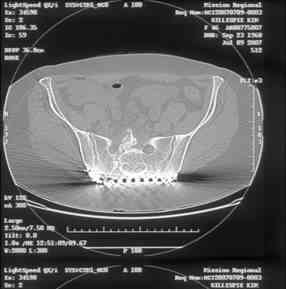

I can't see the axial CT images well enough to detail the potential sacral issues....can you magnify them?

Here is a magnified view. Sorry about the quality but the CT was scanned into our system.